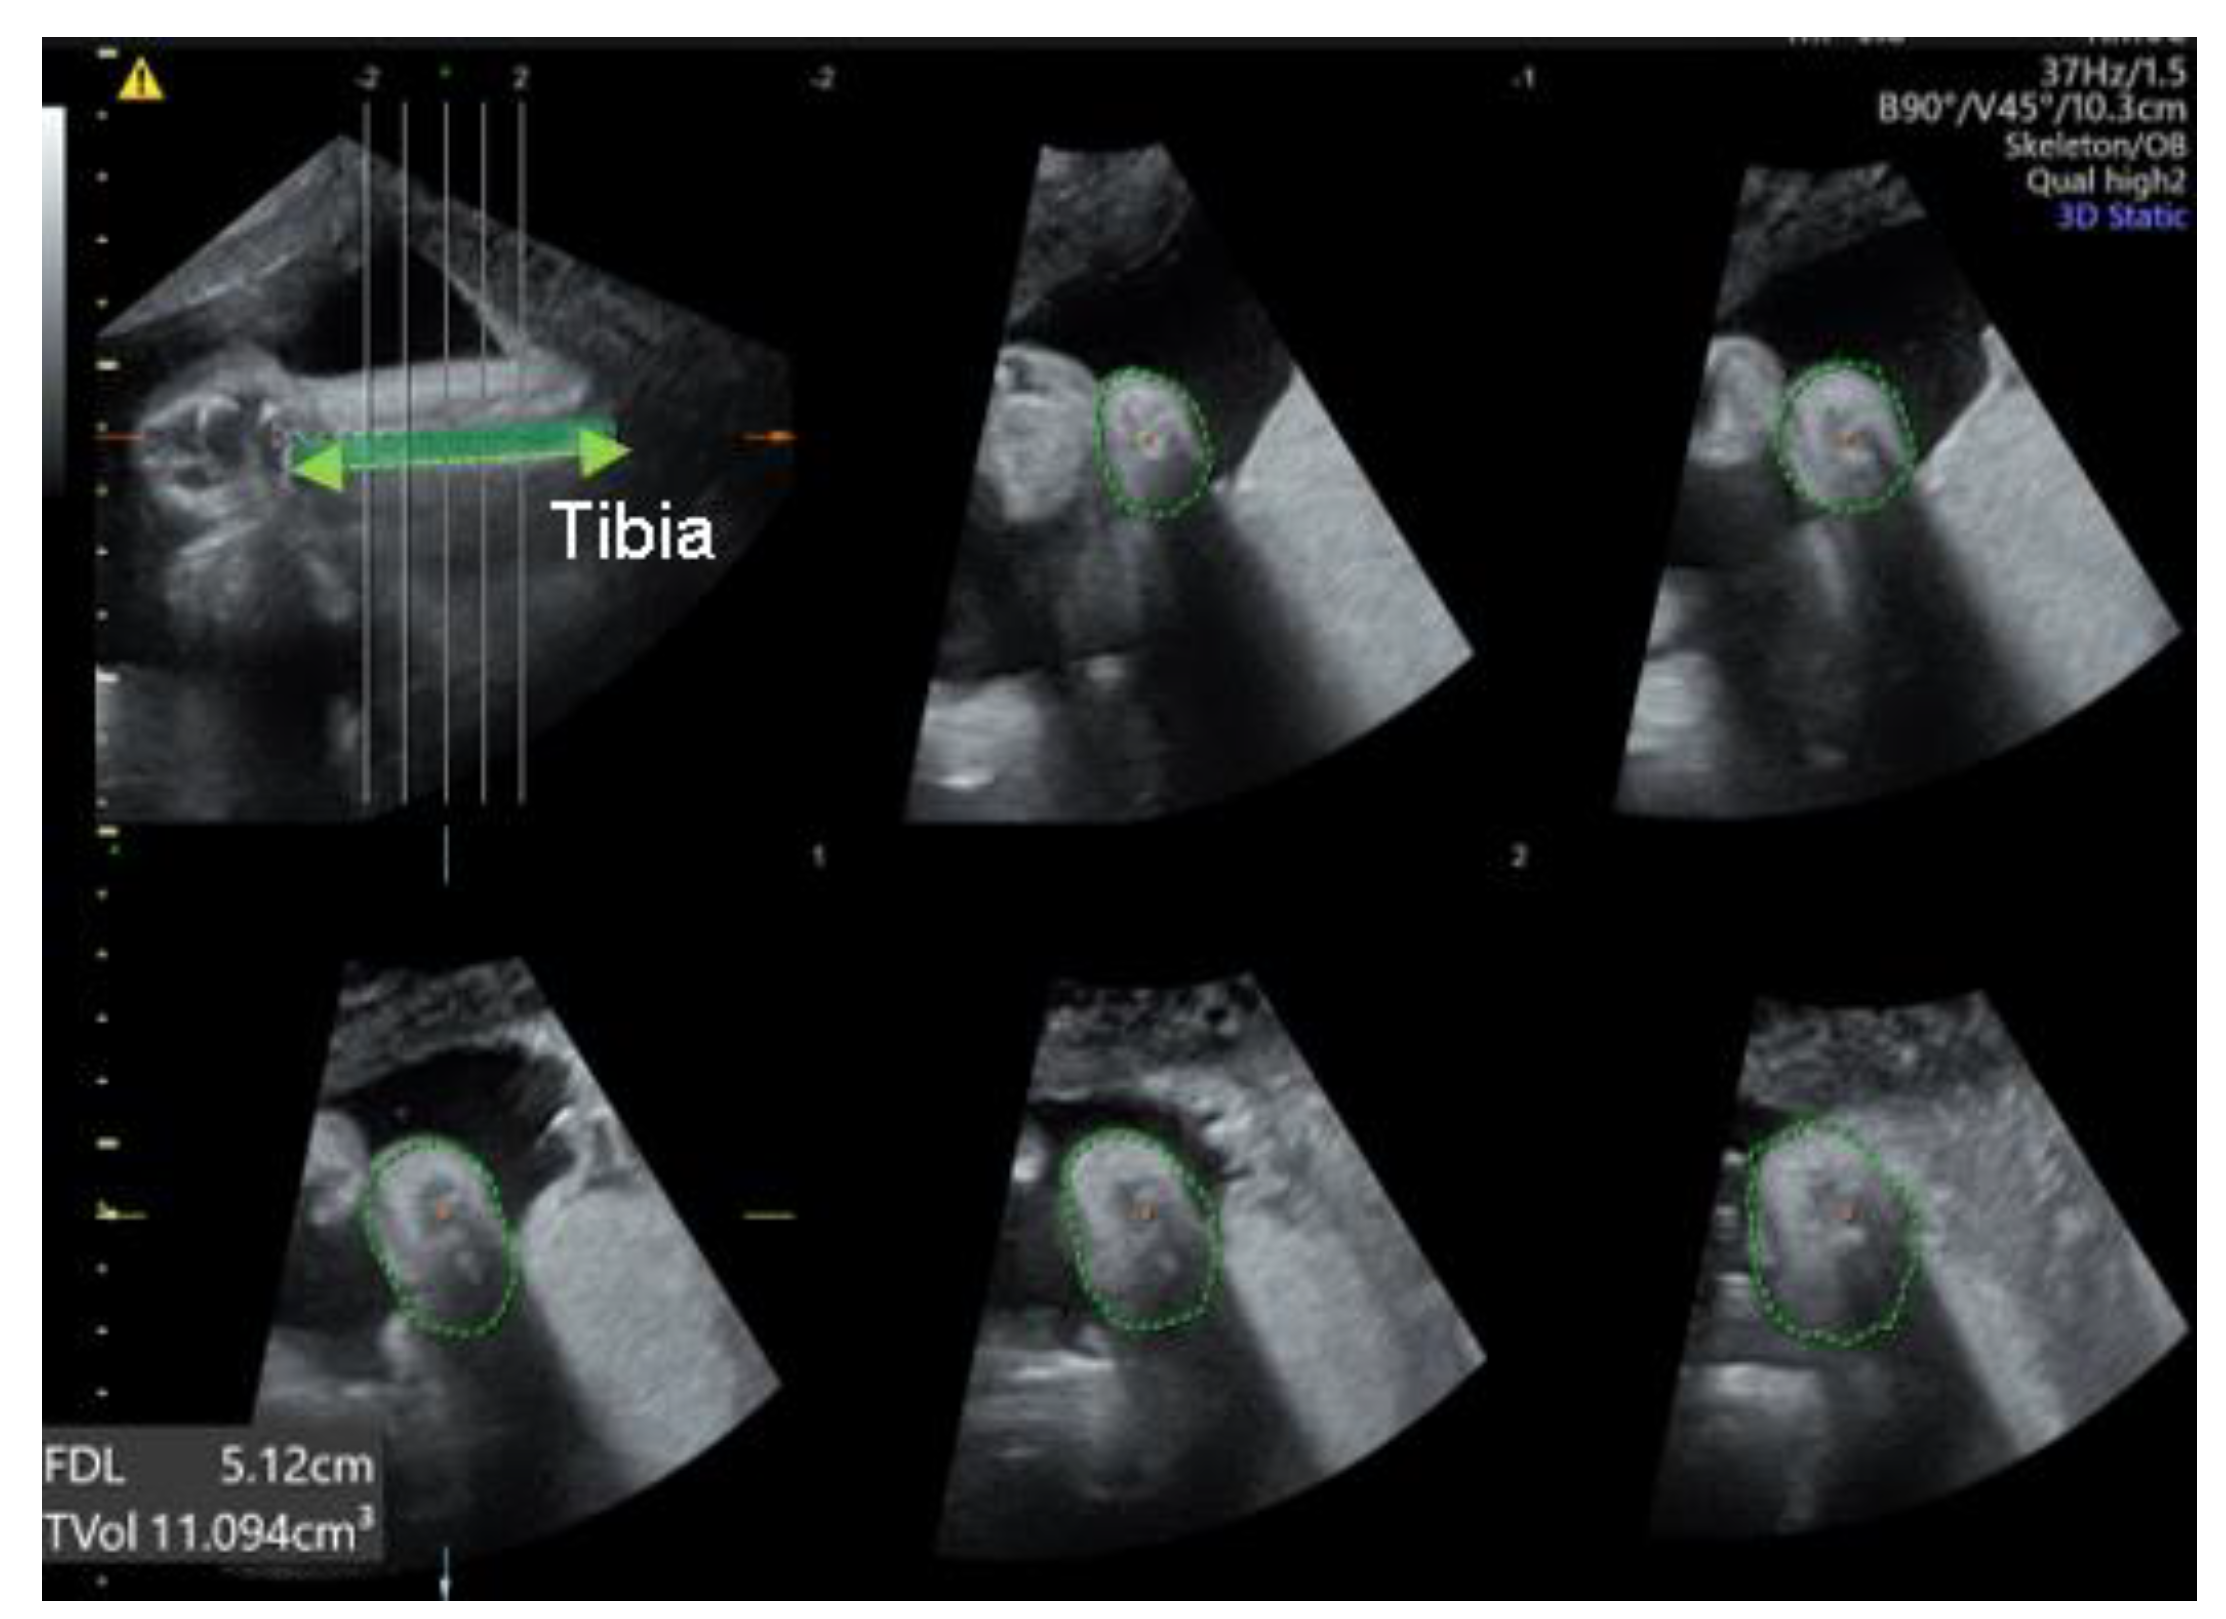

We were able to freely handle the 3D captured image at 360 degrees and reproduce the desired planes, reconstructed the sagittal, coronal (anterior and posterior), and horizontal planes. Below is an explanation of the deviation value measured at each plane (Figure 2). 1. Equinus deviation: the fixation of the foot in a plantar inward position in the sagittal plane. we measured the deviated angle between the line perpendicular to the tibia and the midline of the dorsum. 2. Varus deviation: the medial deviation of the foot in the posterior coronal plane. we measured the angle between the line parallel to the tibia and the midline of the calcaneus 3. Calcaneopedal block deviation: derotation of the calcaneal forefoot block in the frontal coronal plane. we measured the angle between the medial line of the calf and the inner line of the talus.4. Forefoot adduction in the horizontal plane. we measured the angle between the midline of the plantar and the inner line of the big toe. Calf volume and circumference were also measured because calf muscle dystrophy is a significant clinical feature of congenital clubfoot and is one of the scoring factors in the Demeglio method. First, we created a plane in which the tibia and fibula are observed. Second, designating the end of the ossified tibia bone, we divided it horizontally into five sections and measured the circumference using calipers on the skin surface. The largest calf circumference and automatic calculated calf volume were recorded (Figure 3).

Figure 3. The measurement of calf volume and circumference using 3D US. The green dotted line shown in the top left picture indicates tibia. The green circular dotted line shown in the remaining five pictures indicates the calf circumference.